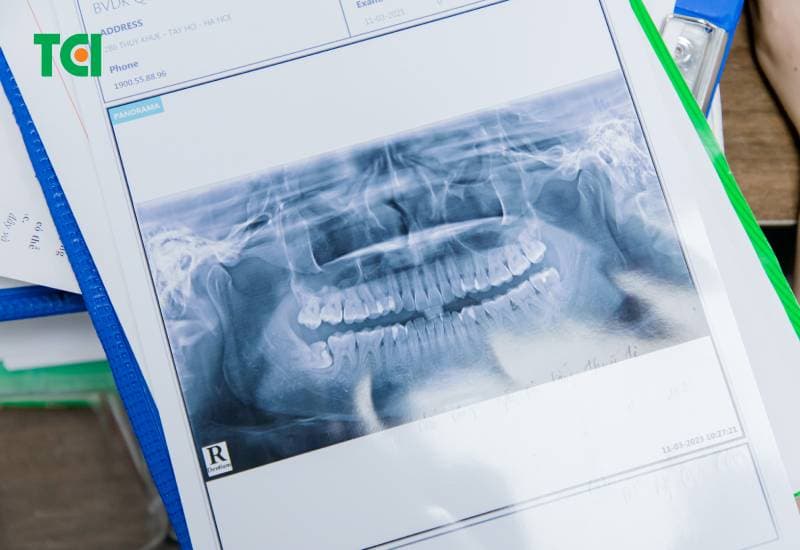

Răng khôn hay còn gọi là răng số 8, là những chiếc răng mọc sau cùng ở vị trí hai bên hàm trên và dưới. Do mọc muộn và thiếu không gian, răng khôn thường mọc lệch, gây ra nhiều vấn đề về sức khỏe răng miệng như sâu răng, bệnh nha chu, ảnh hưởng đến các răng bên cạnh. viêm lợi trùm, áp xe, năng xương hàm,… nghiêm trọng. Do đó, việc nhổ răng khôn là cần thiết trong nhiều trường hợp.

– Răng khôn mọc lệch, mọc ngầm: Răng khôn mọc lệch có thể gây ra nhiều vấn đề như đau nhức, sưng tấy, nhiễm trùng, ảnh hưởng đến các răng lân cận, thậm chí là tiêu xương.